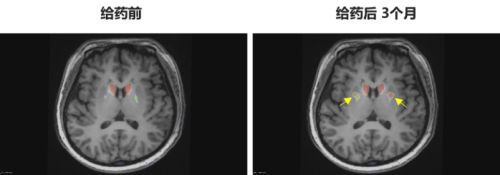

多巴胺能功能成像:神经突触多巴胺能显像是评估人脑黑质纹状体神经元完整性和功能的“金标准”,常用于帕金森病亚临床诊断1-2。接受移植手术3个月后PET-DAT/MRI融合影像明确显示,移植细胞已在患者脑内定植并成功转化为有功能的多巴胺能神经元,双侧纹状体形成显著的de novo新生多巴胺能活性成像(如下图箭头所指), 为功能性治愈提供了最直观的证据。

EOPD患者PET-DAT/MRI融合图像术前与术后三个月对比

注:影像图中黄色箭头指示为NCR201移植后,双侧纹状体出现的新生多巴胺能活性信号,提示移植细胞已定植并高效转化为功能性多巴胺能神经元